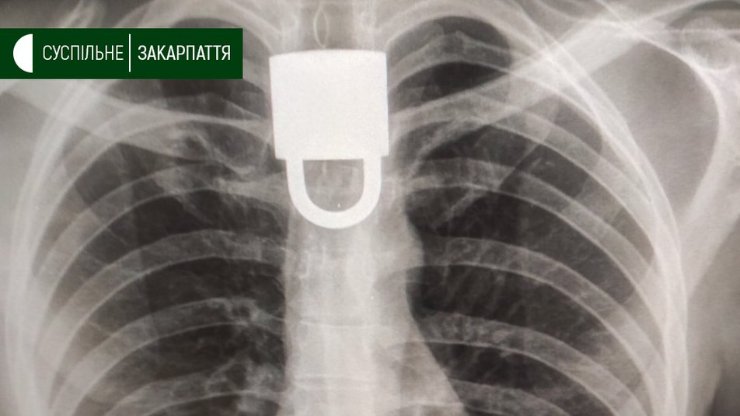

Три тижні тому, каже Курах, у Виноградові, витягнули в пацієнта замок.